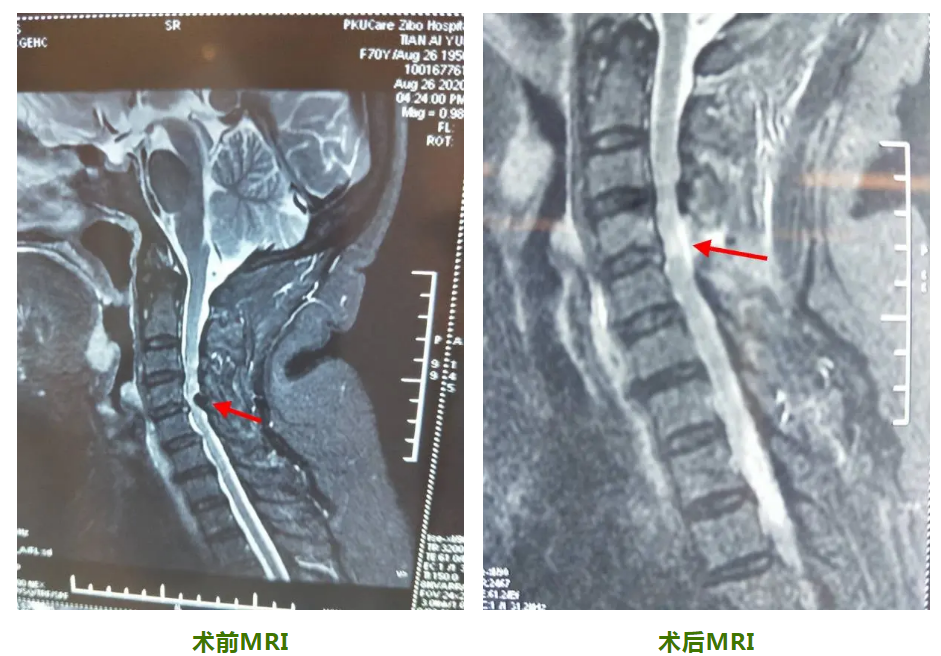

家人聽聞北大醫(yī)療淄博醫(yī)院頸肩腰腿痛診療中心彭昕主任醫(yī)術高超,為多名手腳麻木癥狀的患者解除病痛,于是家人將其送往北大醫(yī)療淄博醫(yī)院。彭昕主任在接診劉女士后,對其進行了詳細的查體,經磁共振檢查后,發(fā)現頸椎間盤突出伴椎管狹窄。結合患者癥狀,按照“疼痛五階梯療法”的原則,已具備手術指征,于是邀請骨外科侯冠華副主任醫(yī)師進行會診。

侯冠華副主任醫(yī)師經仔細查體及參閱病人相關檢查后,診斷劉女士患有脊髓型頸椎病,需要立即進行手術治療。侯冠華副主任醫(yī)師考慮劉女士年齡大,體質差,傳統(tǒng)頸椎開放性手術,不僅創(chuàng)傷大,而且并發(fā)癥多、花費高,于是決定采用脊柱內鏡(Delta系統(tǒng))下頸后路椎板開窗減壓術的微創(chuàng)手術進行治療。

然而家屬對微創(chuàng)手術表示擔心,侯冠華醫(yī)生在與家屬充分溝通后,家屬同意進行手術治療。侯冠華副主任醫(yī)師、劉魯山副主任醫(yī)師與骨科專家團隊進行仔細的術前討論,一致同意脊柱內鏡下微創(chuàng)手術方案,經過完善的術前準備,于9月5日歷經1個半小時,手術順利結束,手術切口僅1.5cm,出血20ml左右?;颊咝g后雙手麻木明顯緩解,第二天便開始下床活動,走路不穩(wěn)癥狀基本消失,不用扶助行器就能行走自如,病人對手術效果非常滿意。術后第三天順利出院。